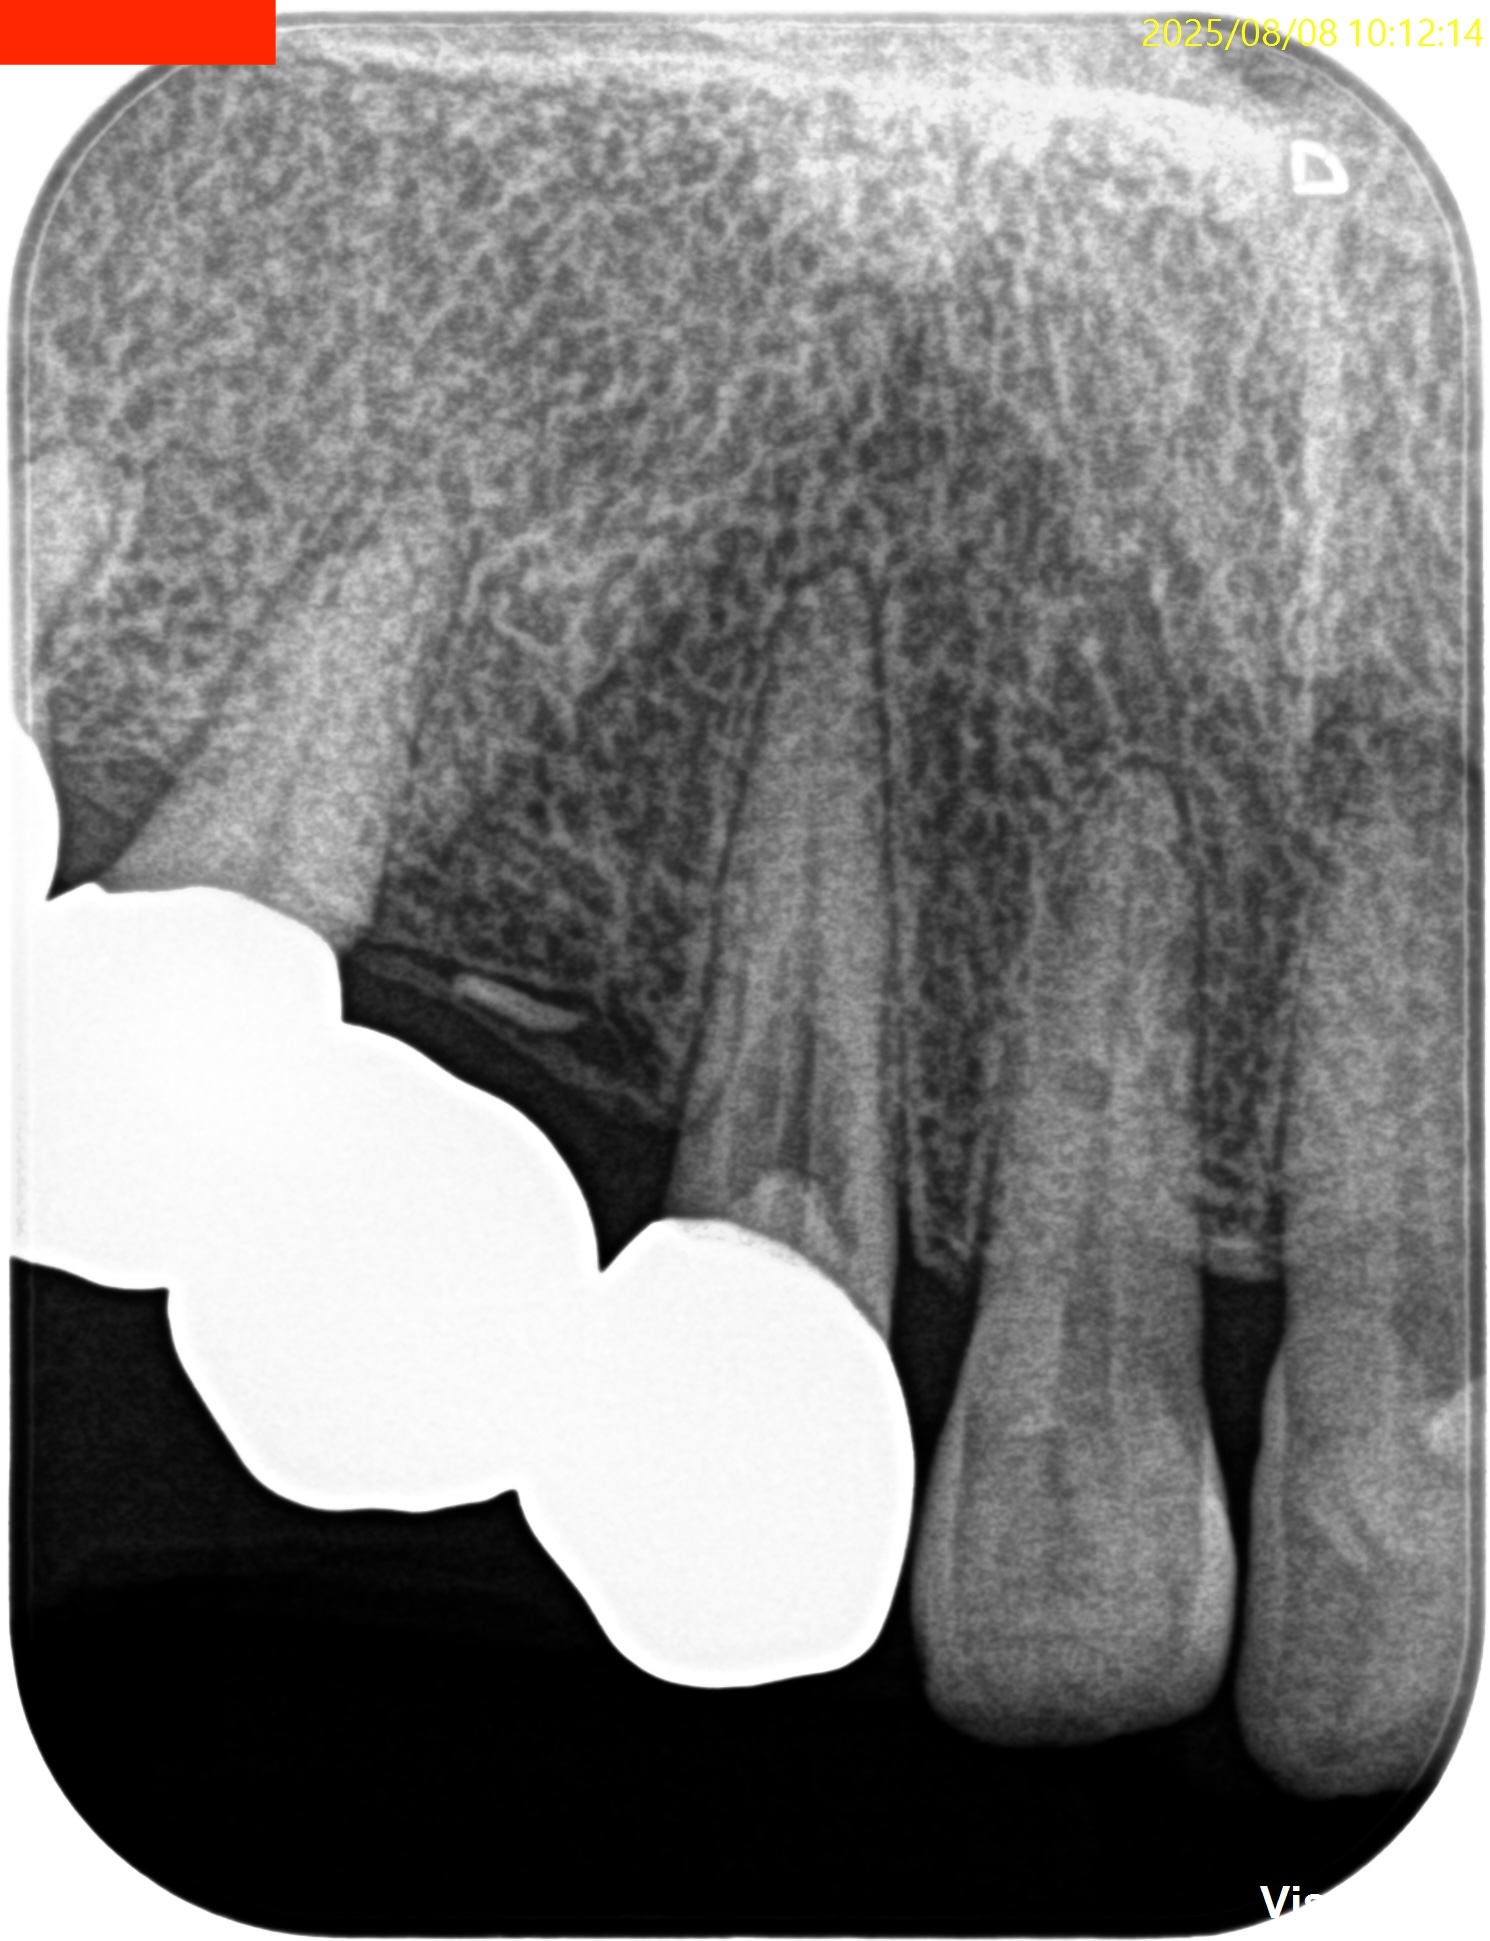

Pre-op Endo test(2025.8.8)

歯牙の表面に外部吸収がある。

学術的には歯髄には及ばないと言われているが画像的には到達済みだろう。

というよりは、根管治療中に出血が起きる可能性が高いだろう。

となれば、根管治療ができない。

その時点で外部吸収のRepairをして根管治療をしなければならない。

が、それが可能だろうか?

不可能であればApicoectomyになる。

Pulp Dx: Chronic apical abscess

Periapical Dx: Symptomatic apical periodontitis

Recommended Tx: Invasive cervical root resorption repair, RCT/Apicoectomy